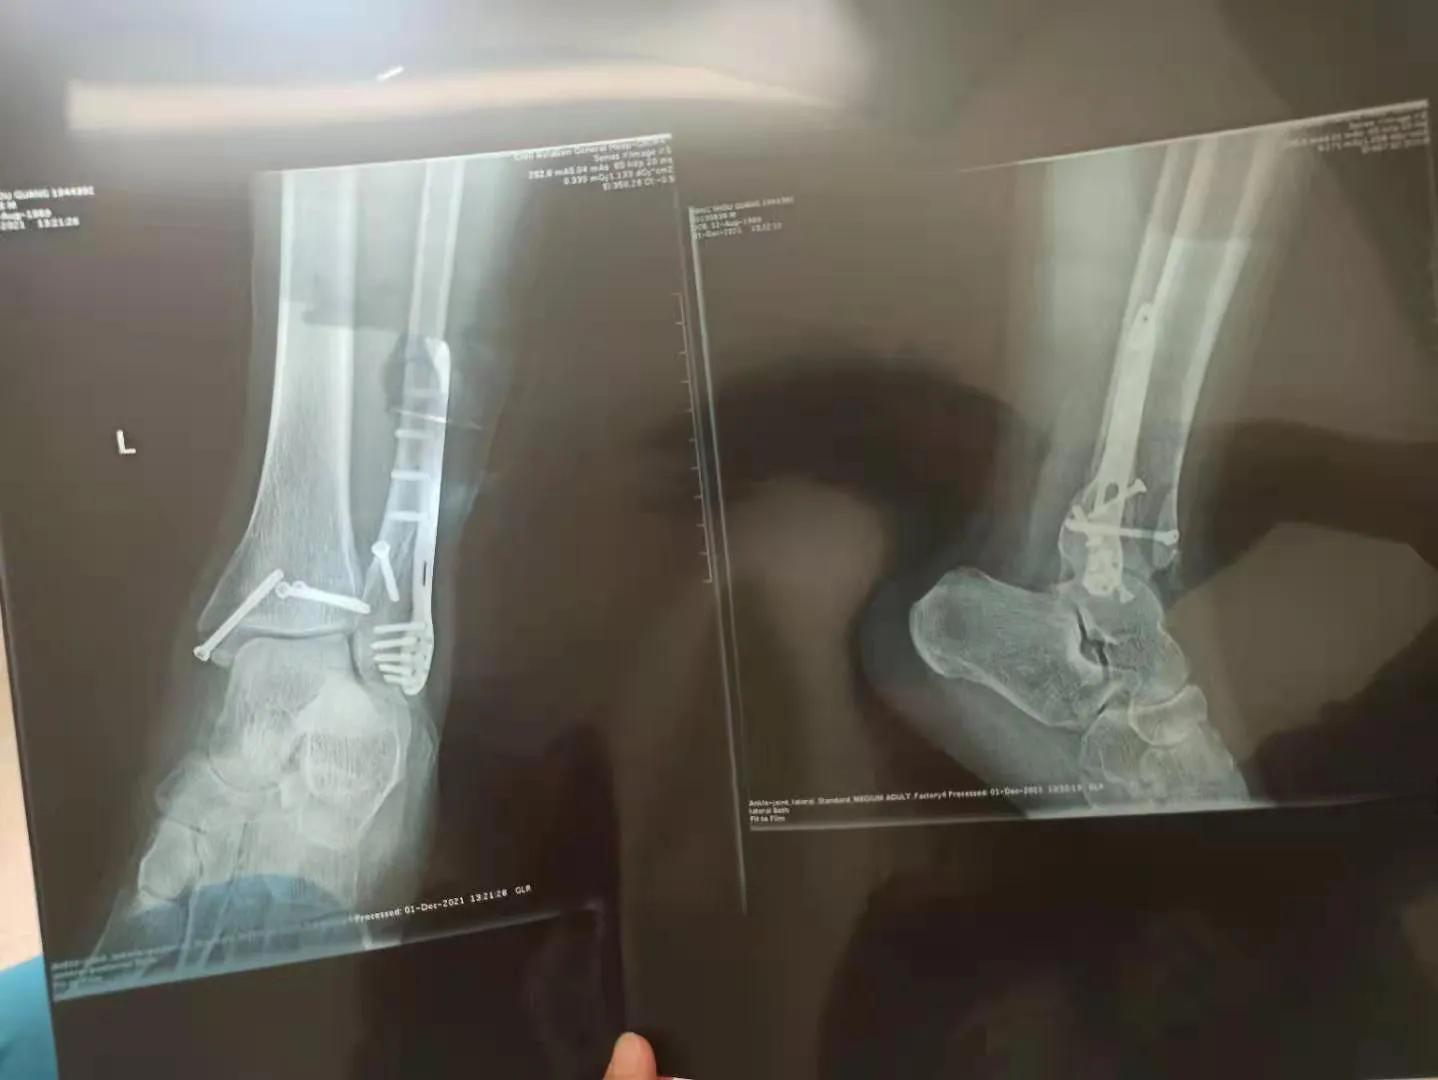

我从未想过,一次普通的篮球比赛会让我陷入长达半年的康复之旅。那天,我在抢篮板时落地不稳,只听到“咔嚓”一声,紧接着是钻心的疼痛。检查结果显示,我遭遇了三踝骨折——这是一种非常严重的脚踝骨折,涉及到内踝、外踝和后踝三块骨头。

医生告诉我,三踝骨折通常需要手术治疗。手术过程中,医生会通过切开复位内固定的方式来固定骨折部位,有时还需要植入接骨板、钉棒或螺钉。幸运的是,我的骨折情况不算太严重,不需要复杂的内固定。